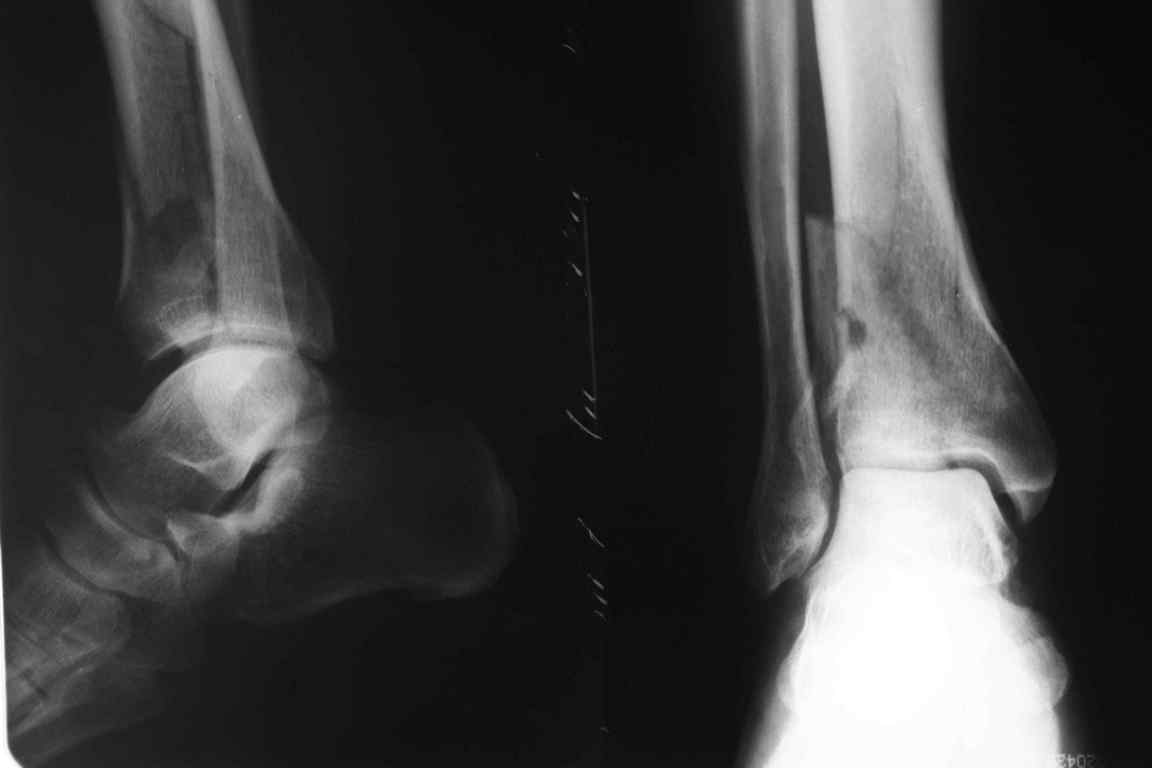

В приложении метафизарный перелом у ребёнка 14лет, с распространением линии перелома на зону роста.

Уважаемый коллега! Обычно, хирургичское лечение переломов пилона начинают с остеосинтеза малоберцовой кости (чего не продемонстрировали коллеги из Новокузнецка). В Вашем случае нет убедительных данных за перелом малоберцовой кости, так что, видимо, этот этап вы пропускаете. После чего переходят собственно к пилону - основные усилия в лечении которого необходимо направить на устранение импрессии (отчетливо видна на боковой R-грамме), затем пластика дефекта ну и накостный остеоинтез платиной, коих достаточно много. Хотел бы предостеречь Вас от: закрытой "малоинвазивной" техники в данном случае, так как для устранения импрессии малоинвазивно необходим определенный опыт и начинать с этого я бы не стал, использовать пластину Pilon Plate-имплант сложный в установке и , опять же, требует определенных навыков. Я бы синтезировал традиционной пластиной "лист клевера" с угловой стабильностью.

В примере показан не перелом пилона, а эпифизеолиз, м/берцовую кость сознательно не фиксировал(длина её восстановлена, ротации нет),у детей стараемся минимизировать операц.травму, несколько позже разрешил полную нагрузку на ногу(4 недели). Но принцип фиксации б/берцовой кости м.б. таким же.

Есть смысл начать с наложения дистрактора голень-стопа. Лигаментотаксис может очень существенно помочь с репозицией. При переломе малоберцовой кости этот подход позволяет не тратить время на ее остеосинтез. Больших участков импрессии суставной поверхности не видно, перелом больше по типу раскалывания. Это делает возможной полностью закрытую репозицию с фиксацией либо аппаратом, либо компрессирующими винтами и аппаратом, либо пластиной малоинвазивно.